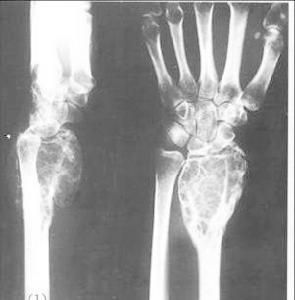

奧爾布賴特綜合症,奧爾布賴特(Albright)綜合症是骨病的一種,可以追溯到1921年,由國外的醫生威爾首先發現。該病是正常骨組織之間被增生的纖維組織代替的一種疾病,可單骨或多骨發病,同時合併皮膚色素沉著、內分泌障礙,這種病的發病率男女比為3:2,年齡從4歲至62歲,病程最長可達36年,發病年齡越小,症狀就越重,尤其是下肢及顱面部。該病的發病機制及病因不明。研究現狀

奧爾布賴特(Albright)綜合症是正常骨組織之間被增生的纖維組織代替的一種疾病,可單骨或多骨發病,同時合併皮膚色素沉著、內分泌障礙,該病的發病機制及病因不明,在中國該病症是由已故的北京大學醫學院汪紹訓教授於1949年發現的,至今國內只有15例被確診為奧爾布賴特綜合症,胡景珍曾接觸過2例奧爾布賴特(Albright)綜合症,但病人的症狀並沒有像小敏這么複雜和嚴重。

骨組織之間被增生的纖維組織2、可單骨或多骨發病,同時合併皮膚色素沉著、內分泌障礙,這種病的發病率男女比為3:2,年齡從4歲至62歲,病程最長可達36年。

3、發病年齡越小,症狀就越重,尤其是下肢及顱面部。